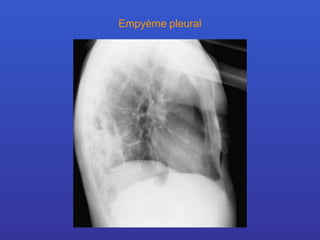

Empyème pleural